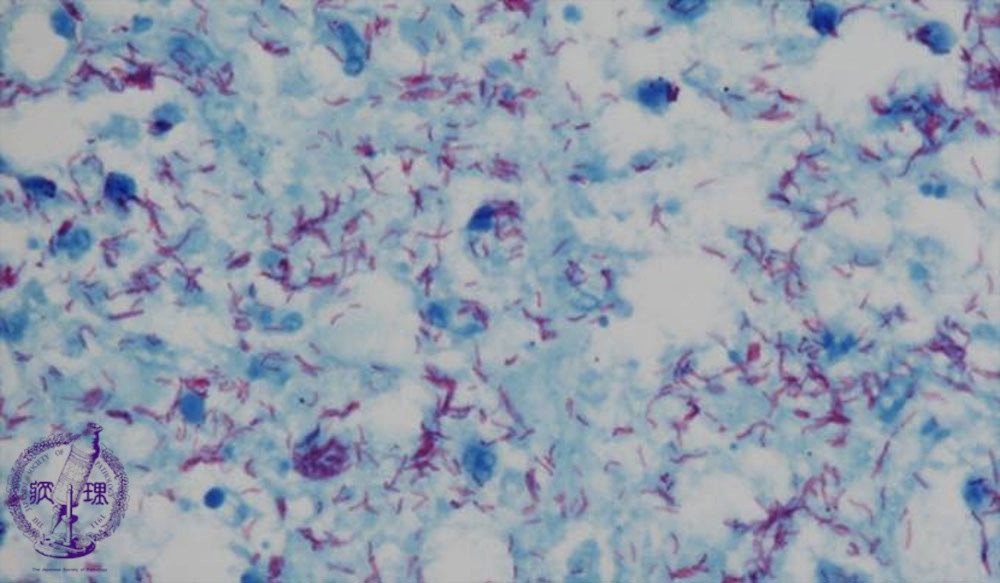

Microscopic view (Ziehl-Neelsen stain, high power view): Acid-fast-stain (Ziehl-Neelsen stain) can selectively highlight mycobacterium. A red stained mycobacterium (tubercle bacillus) is seen.